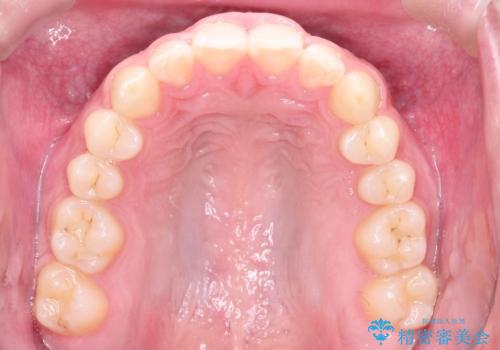

見た目、噛み合わせ及び、治療期間や施術内容に大変ご満足いただきました。